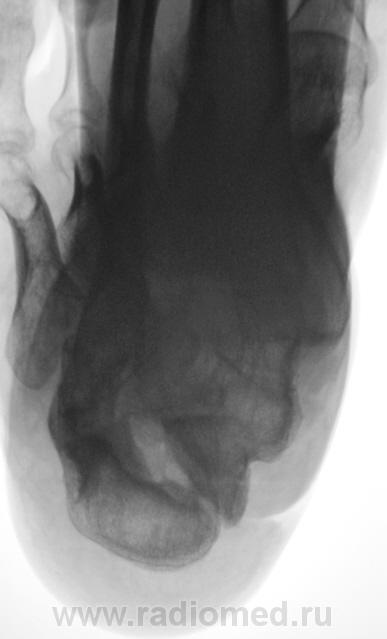

Лечение состояло из "множества рентгенов" и гипса. Срок - 5 месяцев.

Сейчас думают об остеомиелите.

Контуры пяточной кости относительно четкие, разрежение структуры пяточного бугра, в проекции перелома уплотнение структуры кости( имею в виду последние снимки).Клиника остеомиелита есть?

Во-первых, деформация пяточной кости; во-вторых, отсутствие консолидации, через некоторое время и ложный сустав сформируется. Неоднородное уплотнение костной структуры в теле кости может быть обусловдено как остеомиелитом, так и перераспределением нагрузки.

Признаков остеомиелита не вижу, только консолидир перелом с неуд стоянием отломков.